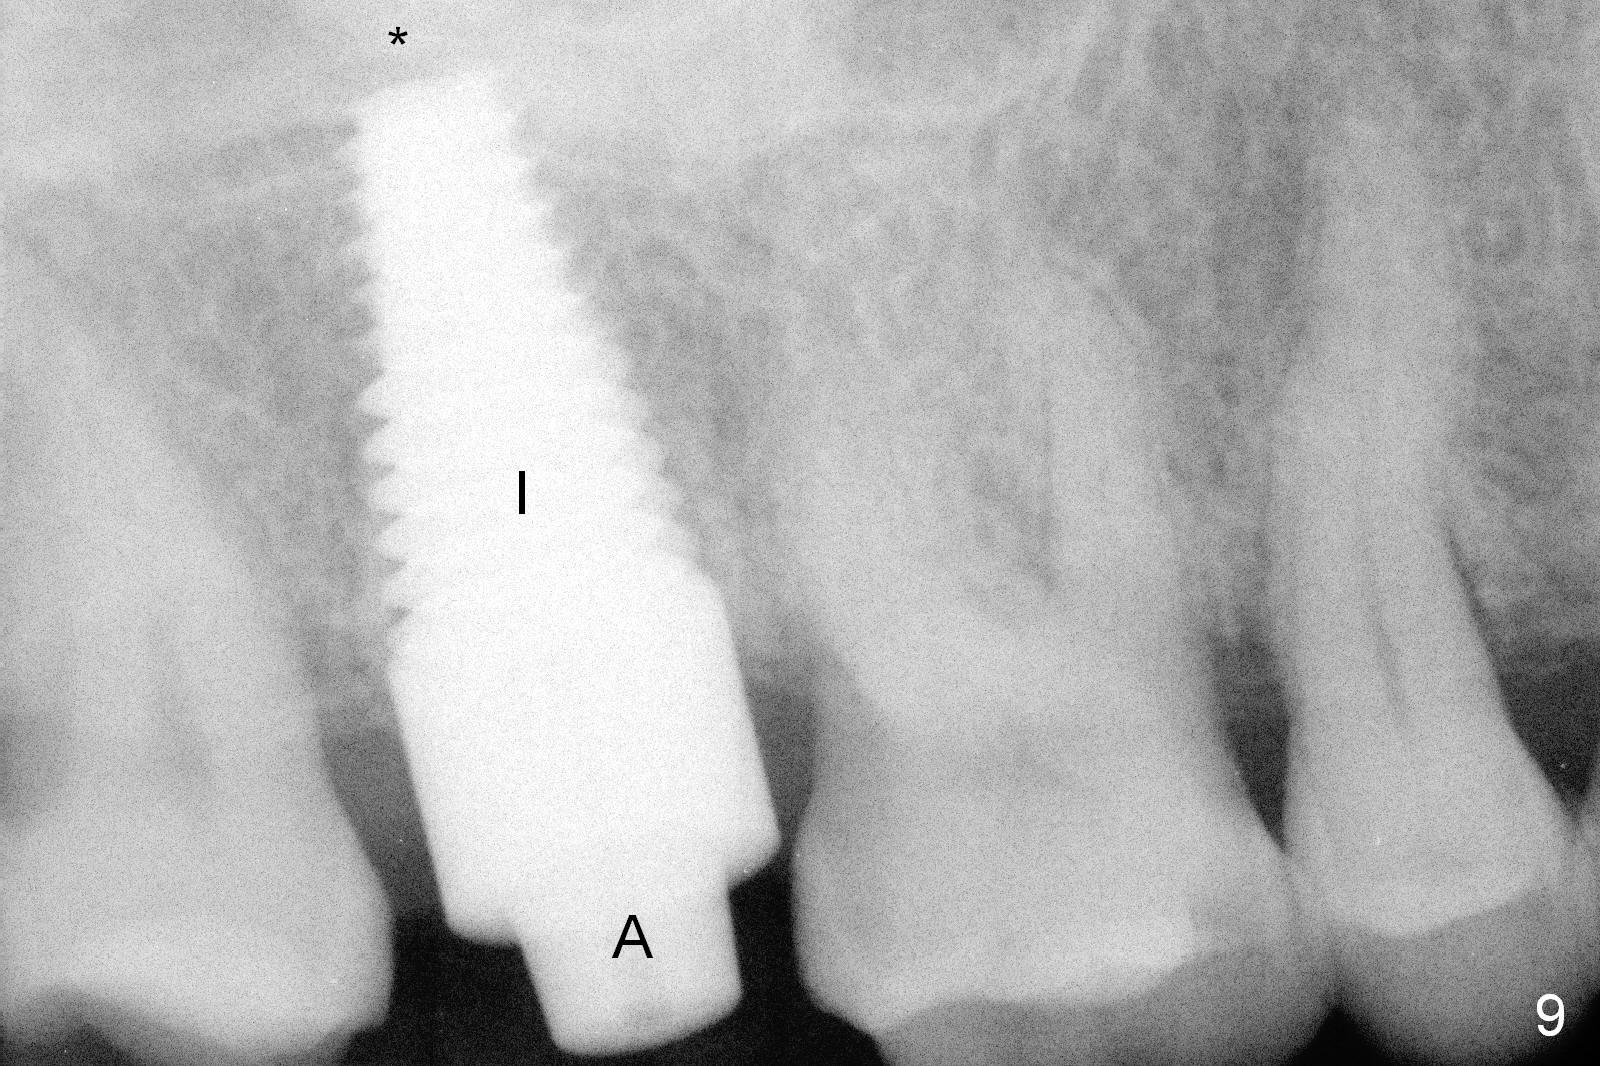

Osteotomy for immediate implant is initiated with a 2 mm pilot drill (Fig.6b red arrow) in the coronal end of the buccal slope of the septum (center of the socket). Once the drill gets initial penetration, the trajectory changes to the long axis of the tooth (Fig.6c). Then PA is taken with a parallel pin (Fig.7). It appears that the depth is not enough; there is bone apical to the pin. As osteotomy increases in diameter, burs may be deviated buccally due to the septal buccal slope (to be discussed below). With longer osteotomy, the deviation may be less. Osteotomy is deepened (Fig.6d). From this moment on, nose blowing test is done after each step. The result is all negative. As drill diameter increases, they do deviate buccally (Fig.6e arrow), since there is less bone contact buccally than lingually (compare Fig.6e,f). With the same reason, smaller tapered taps (Fig.6g pink, 5 and 6 mm) tend to be mobile buccally (arrow). When a large tap (7 mm) is inserted (Fig.8), there is no buccal mobility. It appears that the tap contacts more of the buccal plate (Fig.6h), but the coronal end of the tap is buccal (Fig.6i, pink circle). At each step of osteotomy, the coronal end of a bur or tap should be pushed as lingual as possible so that the final tap is favorable for restoration (Fig.6j). Sinus lift is done (Fig.6k red circle; Fig.9 *) before placement of 7x17 mm implant (I, >60 Ncm). Since the palatal socket is not associated with implant stability, it is closed by collagen plug (Fig.6l, blue area). As extra precaution, bone graft is placed around the coronal portion of the tissue-level implant (Fig.6l red circles), followed by collagen dressing.

Probably due to bruxism, there is limited vertical restorative space. The margin is subgingival except buccal (Fig.10,11). An immediate provisional (Fig.12 P) appears to have to be fabricated to prevent soft tissue from covering the margin during osteointegration. It is our intention to make gingival envelop larger than the definitive crown cervix. It would be easier to remove a permanent cement later on for peri-implantitis prevention.